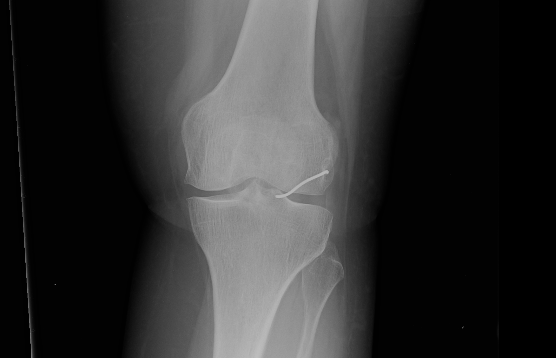

כעבור כשנתיים, ולאחר שספגה מהלומה באזור הברך, החלה האישה לסבול מכאבים עזים ונבדקה על ידי אורתופד. זה שלח אותה לצילומי רנטגן, וגילה, למרבה ההפתעה, כי בברך ישנה פיסת מתכת, והיא זו שככל הנראה גרמה לכאבים. האישה הופנתה לניתוח, שלישי במספר, ובמהלכו הוצא מברכה תיל מתכת באורך 3.5 ס"מ.